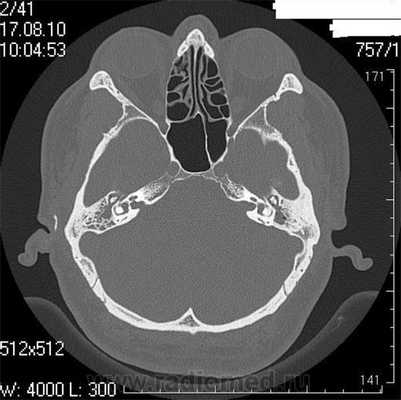

Что покажет КТ височных костей

Во время КТ получают послойные снимки височной кости и окружающих тканей в трех плоскостях. Толщина среза составляет всего несколько миллиметров, что позволяет врачу-рентгенологу рассмотреть не только все анатомические образования, но и минимальные патологические изменения.

На полученных снимках хорошо видны следующие структуры:

пирамида височной кости;

ячейки и антрум сосцевидного отростка;

улитка, преддверие, передний и задний полукружный каналы;

слуховые косточки среднего уха;

стенки наружного слухового прохода;

Снимок (томограмма) височных костей в осевой проекции